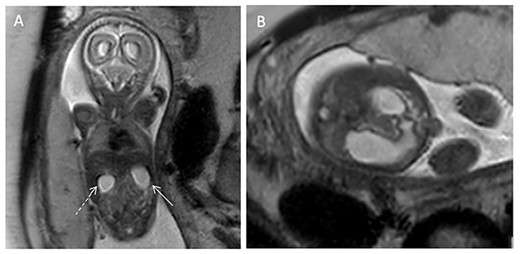

A 24-year-old G2P0010 woman was referred to our fetal care center at 21- and 2/7-weeks’ gestation following routine ultrasound that identified ascites, dilated small intestine and absent versus right-sided stomach. Fetal ultrasound performed at our institution demonstrated a dilated stomach with possible ‘double-bubble’ sign (Fig. 1). Fetal magnetic resonance imaging (MRI) confirmed dilation of the stomach and proximal duodenum without clear distinction between the two structures (Fig. 2), suspicious for duodenal atresia. Polyhydramnios was not seen on either ultrasound or MRI. She was scheduled for amniotic fluid index (AFI) evaluations (Table 1) and biophysical profiles (BPP) every 2 weeks with monthly growth ultrasounds, and induction was planned at 39-weeks’ gestation. At 30- and 2/7-weeks’ gestation, her AFI was mildly elevated at 29.7 cm (normal 5–25 cm). The ‘double-bubble’ sign was not identifiable on any follow-up evaluation. At 34- and 5/7-weeks’ gestation, she presented with decreased fetal movement. Her BPP was abnormal with absent fetal breathing episodes and a non-reactive non-stress test, necessitating further surveillance and ultimately Cesarean section. The infant was initially apneic, cyanotic without grimace and bradycardic. There was no response to continuous positive airway pressure ventilation requiring intubation with improvement in hemodynamic status. Oro-gastric sump tube placement was attempted but could not be advanced past the proximal esophagus. Radiographs noted coiling of the sump tube within the proximal esophagus and a gasless abdomen. On day of life two, the infant was taken to the operating room for rigid bronchoscopy and laparoscopic gastrostomy tube placement. Bronchoscopy demonstrated normal tracheal and bronchial anatomy. The bronchoscope was used to evaluate the esophagus and confirmed a blind-ending esophageal pouch. A gastrostomy tube was placed laparoscopically without issue but upon insufflation of the stomach, froth was noted along the lesser curve just proximal to the pylorus. A supra-umbilical midline incision was made to further evaluate, and a gastric perforation was noted. A red rubber catheter was passed through the perforation and met obstruction within the second portion of the duodenum. The perforation was repaired, and a standard duodenoduodenostomy was performed.

(A) T2-weighted coronal fetal MRI image demonstrating dilation of the stomach (solid arrow) and duodenum (dashed arrow). (B) T2-weighted transverse abdominal fetal MRI image demonstrating a dilated stomach in continuity with the dilated duodenum.